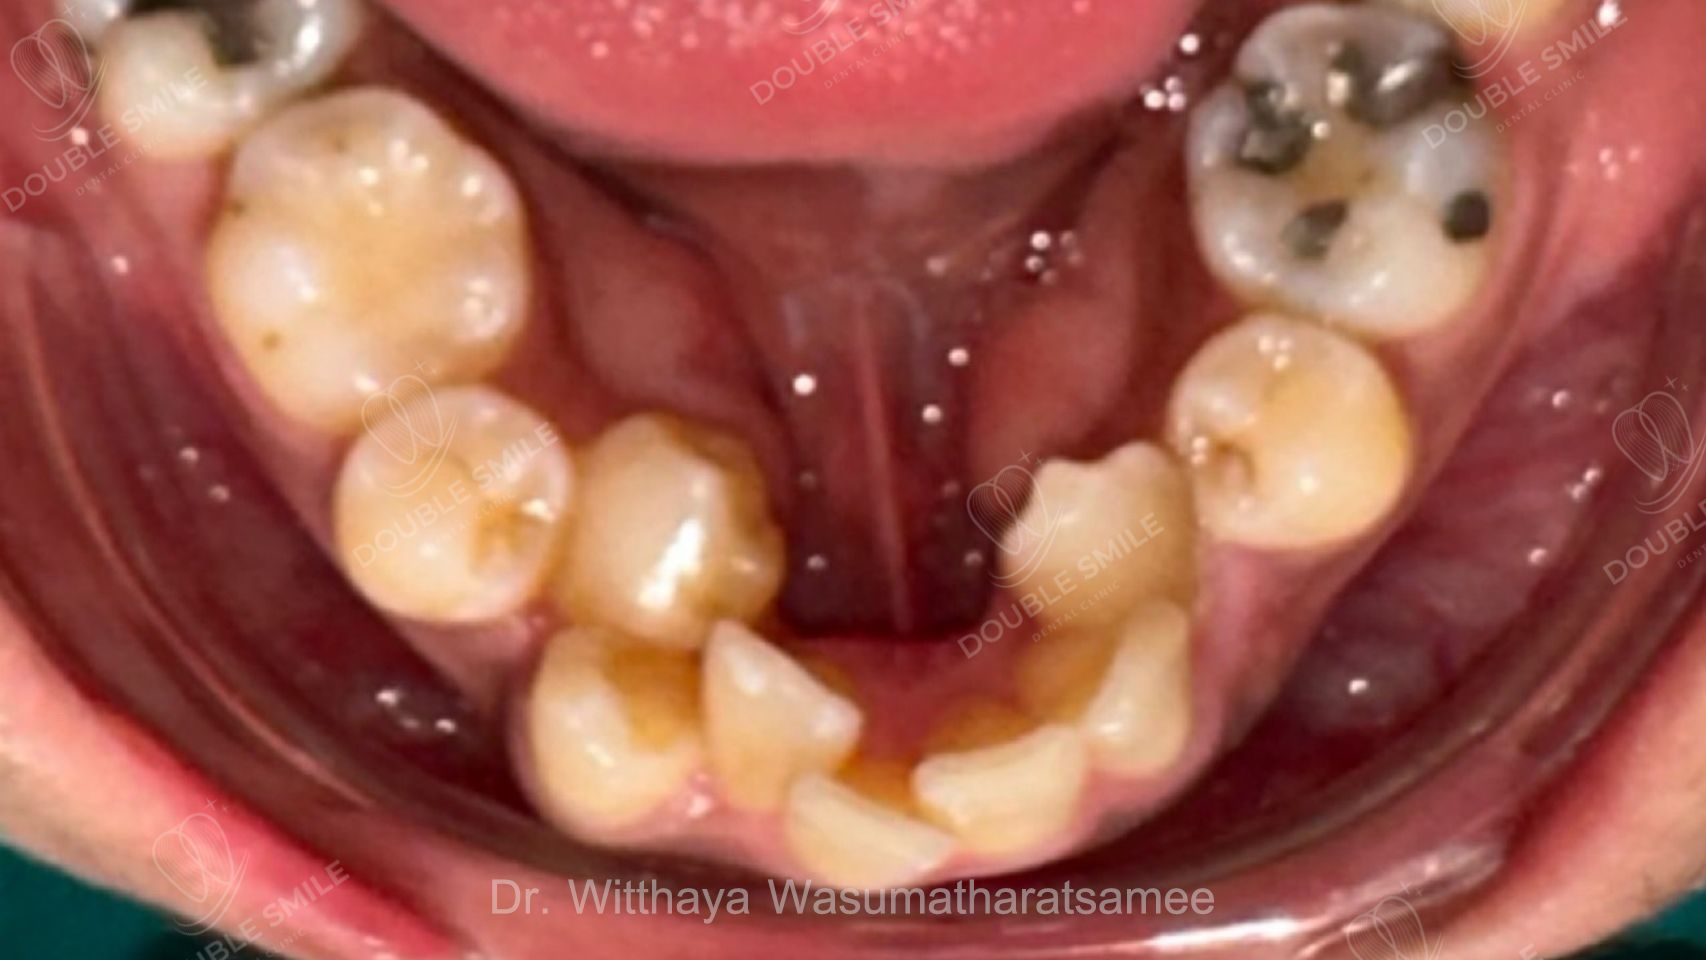

Before

Case Review

Before & After